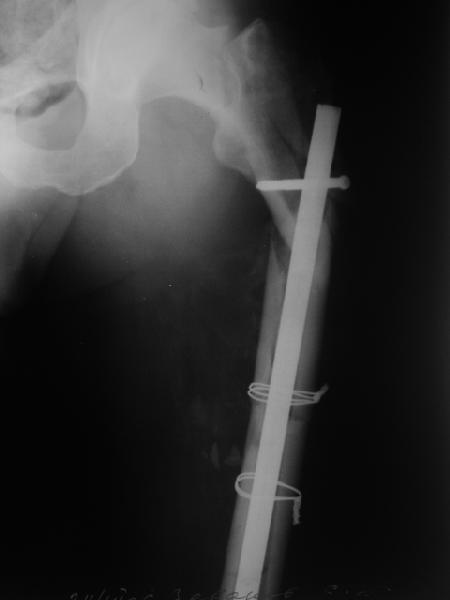

В общем, сделали. См. приложение.

Длина и из-за этого ось получились не совсем такие, как хотелось бы, все-таки срок после той операции уже 6 недель. Может быть, стоило провести дистракцию аппаратом неделю-другую. Заранее спасибо за комментарии и критику.